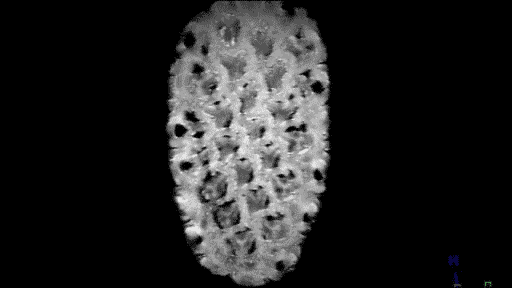

Quizás no sea lo más ortodoxo, pero no podemos negar su componente curioso y llamativo. Seguramente pocos nos imaginaríamos que una fruta de la pasión o la raíz de un apio tienen en su interior un aspecto muy similar al del cerebro. O que las fresas se parecen a un panal de miel. Aclaremos el misterio: esto ocurre cuando las frutas son observadas a través de una resonancia magnética.

Andy Ellison, técnico en resonancias magnéticas del Centro de Imágenes Biomédicas de la Escuela de Medicina de la Universidad de Boston, se ha propuesto enseñarnos de este modo cómo son las entrañas de las verduras y las frutas que comemos a diario. Para ello, ha utilizado la tecnología médica avanzada con la que trabaja para capturar las secciones transversales de estos alimentos, de la misma manera que cada día se hace con el cerebro humano, las rodillas o la columna.

El resultado, que recoge en su blog Inside Insides, son unas fascinantes imágenes y GIFs que nos muestran las frutas y las verduras desde otro punto de vista. Desde un interior tan llamativo y adictivo como lo pueden ser sus colores, formas y sus texturas. La colección es amplia y da para todo tipo de evocaciones, porque por el escáner de Ellison –en concreto, una Philips 3 Tesla MRI, explica– han pasado todo tipo de alimentos, desde los más comunes como las cebollas, los pimientos, los tomates o los plátanos, hasta lichis, la jaca (también conocida como jackfruit, uno de los frutos más grandes del mundo), la fruta del dragón o el kiwano (o pepino africano).